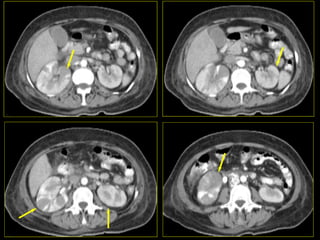

Caso # 7 ♀ , 45 años,  dolor abdominal difuso, sin poder determinarse la causa clínicamente por lo que se envía a TC para búsqueda de la probable causa de dolor. Estudio en fases arterial, venosa y excretora, mostrándose cortes axiales.

FASE ARTERIAL

FASE VENOSA

FASE EXCRETORA

Hallazgos Caso # 7: Hay un área triangular de disminución de la atenuación en la parte posterolateral del  riñón izquierdo, las cuales se demuestran en fases contrastadas, y en fase excretora muestran persistencia del medio de contraste, en relación con proceso inflamatorio focal.